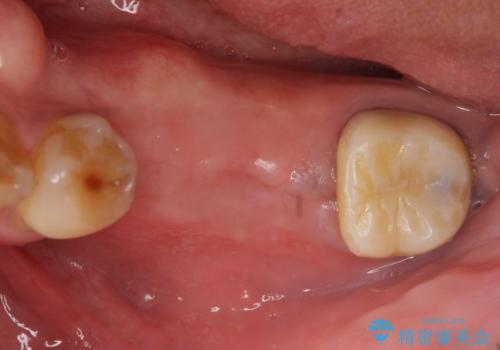

- 左下奥歯が虫歯で抜歯になってしまったため、インプラントにしたいといらっしゃった方の症例です。

欠損部位である左下5、6番目にインプラントを埋入し、オールセラミッククラウンによる補綴を行いました。

カスタムアバットメントは患者様それぞれの歯茎に合わせて製作されたオーダーメイドのアバットメントです。

既製のアバットメントに比べ適合がよく、高い清掃性を誇ります。